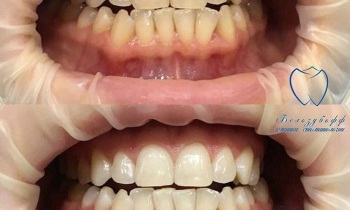

Наш ортодонт Евгений Владиславович Алексеев использует в своей работе не только стандартные общепринятые методики, но и самые современные, такие как аппарат Марко Роса